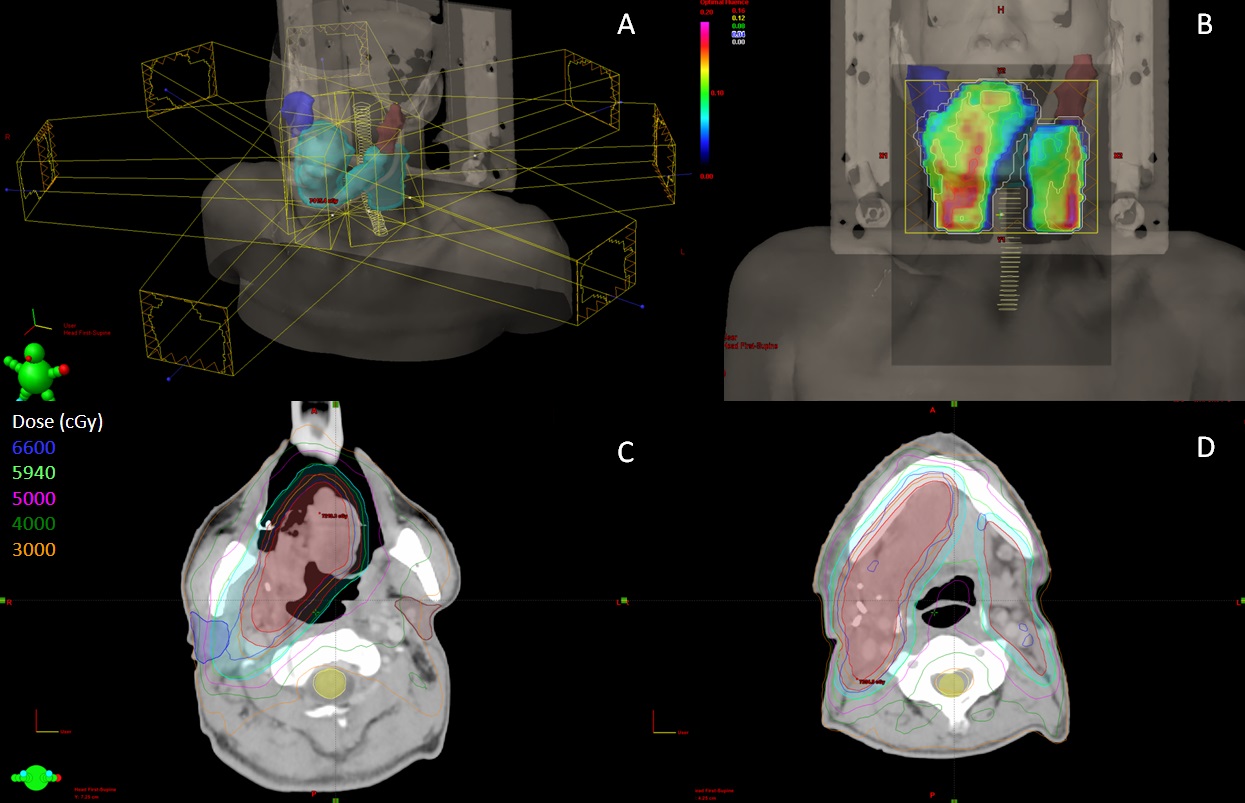

強度調控放射治療(IMRT)強度調控放射治療(Intensity modulated radiation therapy, IMRT)是以數個治療角度(以三到九個治療角度最為常見),每個角度分割成許多獨立小射束,藉由小射束強度之調節,使高劑量區域在三維方向,能依據腫瘤形狀及深度分布,同時可減少週圍之正常組織的照射劑量。此技術相較於三度空間順形放射治療技術,更能進一步提高腫瘤部位之劑量包覆率,以達到更好的腫瘤控制率及患者的生活品質。

左圖(A)七個治療角度;(B)射束強度分佈圖,圖中為其中一個治療角度之射束強度分佈圖;(C)(D)劑量分佈圖,線條代表劑量,色塊區域代表解剖位置。紅色與淺藍色區域為腫瘤,黃色區域為脊髓,藍色及咖啡色區域為唾液腺。